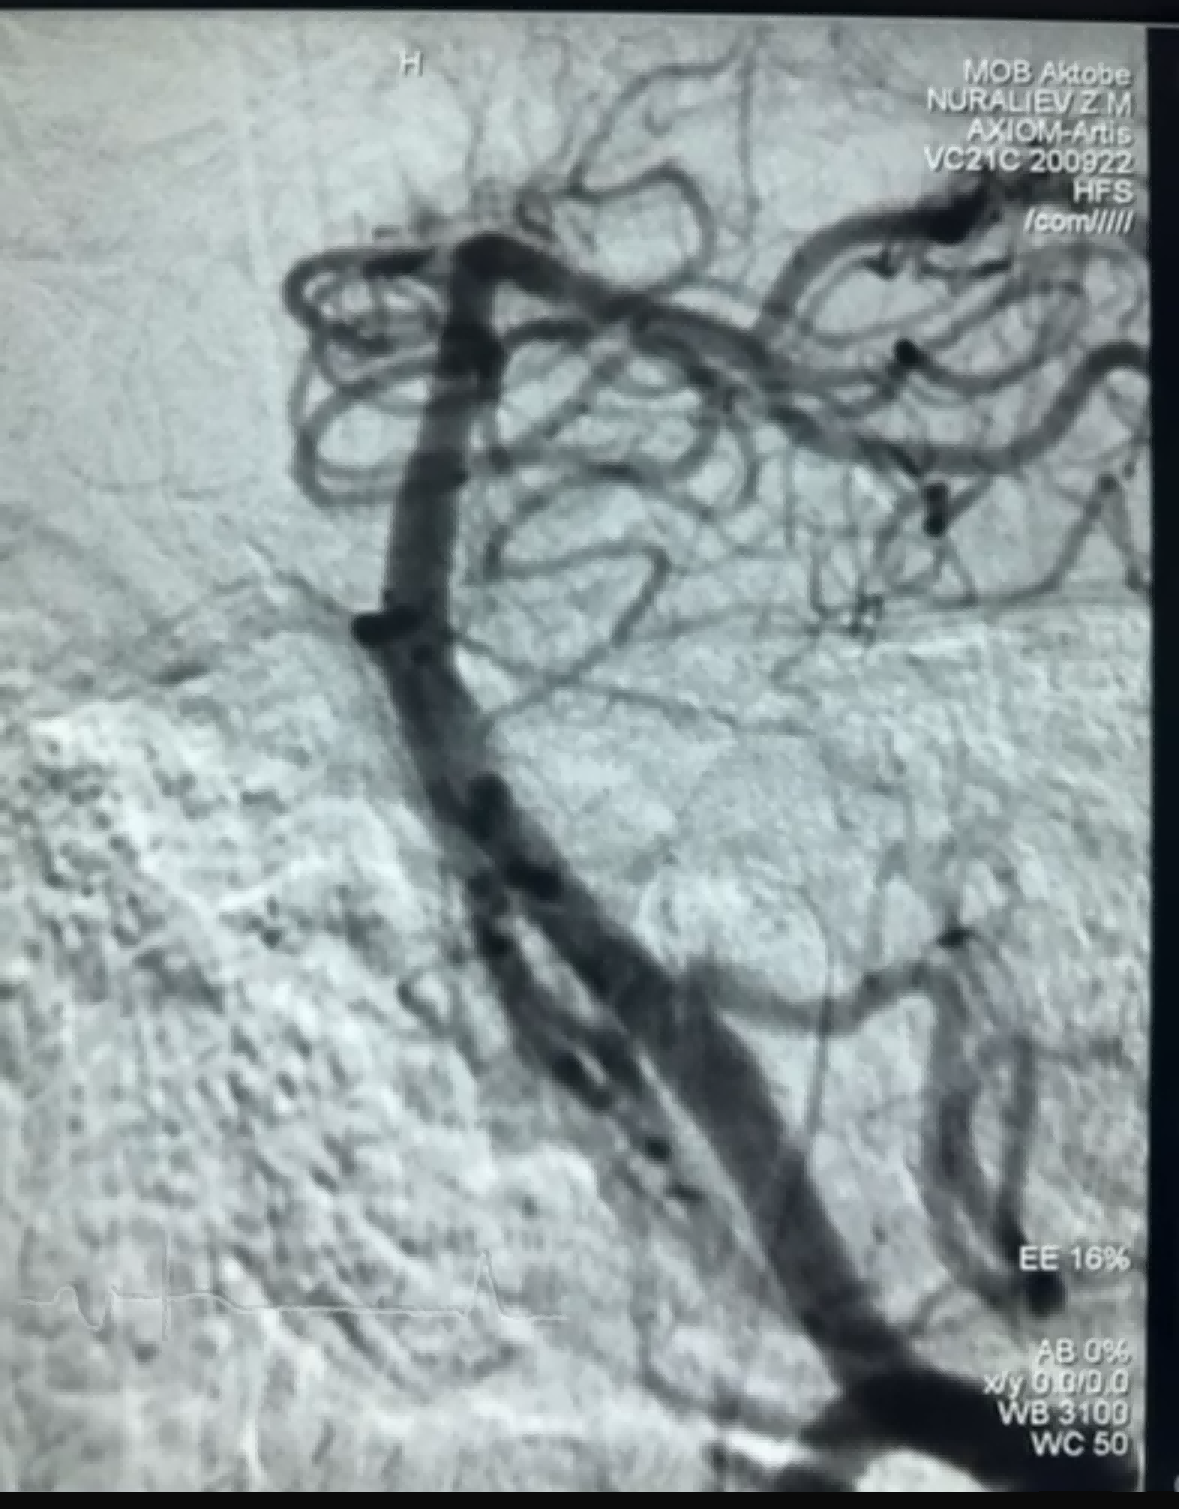

Récemment, un cas de thrombectomie a été réalisé avec succès à l'aide du Dredger Stent Retriever de NeuroSafe Medical Co., Ltd. Le Dredger Stent Retriever est doté d'une pointe souple non invasive, ce qui réduit considérablement le risque de lésion de l'intima, et d'une conception de trou de forme spéciale unique qui capture les caillots sanguins principalement en serrant les changements d'espace.